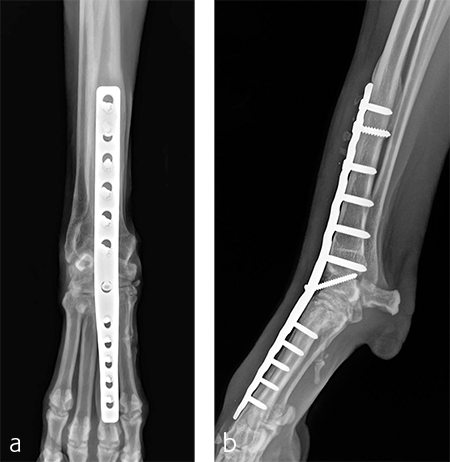

Treatment with a splint for several weeks resulted in no improvement. A pancarpal arthrodesis was performed with the 2.7/3.5 Pancarpal Arthrodesis Plate and a combination of standard cortical and locking screw fixation. An autogenous cancellous bone graft was collected from the left proximal humerus and placed at all joint levels.

Immediate postoperative images confirmed anatomic alignment and adequate carpal extension (Fig 10). At the 11-week postoperative follow-up examination, functional recovery was very good with images revealing stable implants and healing of the arthrodesis (Fig 11). The dog was then allowed to return to normal activity.